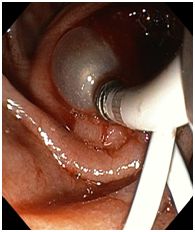

Endoscopy and colonoscopy are safe and accurate procedures used to directly examine the digestive tract and detect the root cause of chronic acidity, GERD, abdominal pain, bleeding, and bowel irregularities. These minimally invasive tests help identify ulcers, inflammation, infections, polyps, strictures, and early cancerous changes.

At Sapphire Gastroenterology Center, modern endoscopic equipment ensures precise diagnosis and, when required, therapeutic intervention during the same procedure. Based on findings, targeted treatment plans are created, including medication, diet guidance, and preventive strategies. Early diagnosis through endoscopy and colonoscopy plays a crucial role in preventing serious complications and improving long-term digestive health.